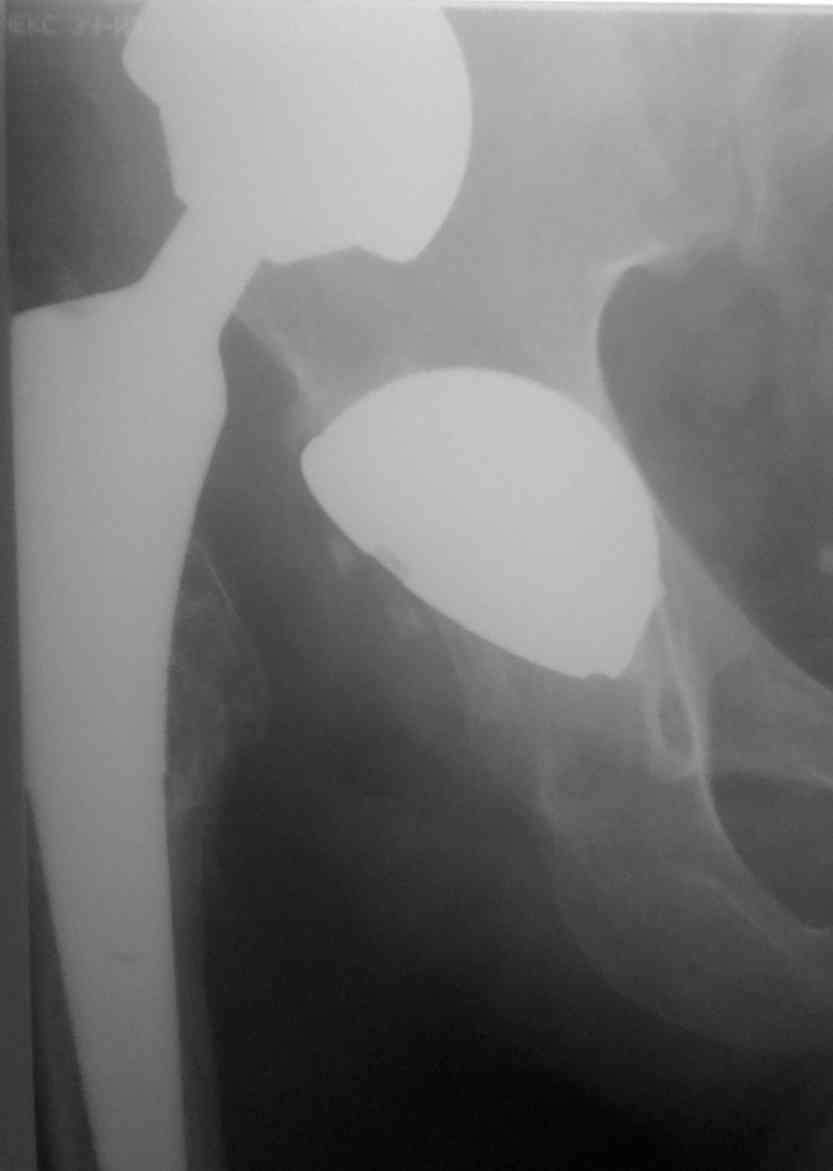

[Ortho] Застарелый вывих эндопротеза

Хотелось бы получить совет по тактике в отношении непростого пациента.

Пациент 40 лет, оперирован в апреле 2009. вывих в мае 2009г.За

медпомощью не обращался. попыток устранения вывиха не было. ходит на

костылях без опоры на конечность.